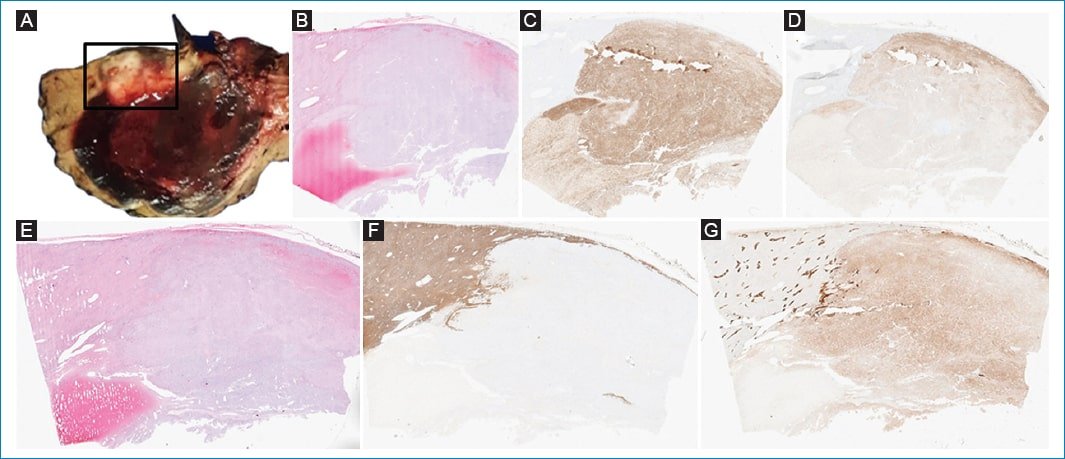

Posteriormente se realizó una hepatectomía izquierda ampliada. El análisis histológico reveló una lesión con un patrón de crecimiento expansivo y alta densidad celular, con extensas áreas de hemorragia intranodular (Fig. 4). Había evidencia de una rica red vascular intratumoral y zonas circunscritas de tejido adiposo. Se diagnosticó como AMLEH con extensas áreas de necrosis hemorrágica. El postoperatorio transcurrió sin incidentes y la paciente fue dada de alta a la semana.

Figura 4. Macroscopia (A) e histopatología con hematoxilina y eosina x40 (B). El análisis inmunohistoquímico reveló células inmunorreactivas para Hmb-45 (C) y Melan-A (D). En otra sección con hematoxilina y eosina x40 (E), se observa la ausencia de reactividad para HEPAR 1 (F) y la reactividad difusamente positiva para glutamina sintetasa (G). Los hallazgos hacen el diagnóstico de AMLEH. No se encontró atipia celular.